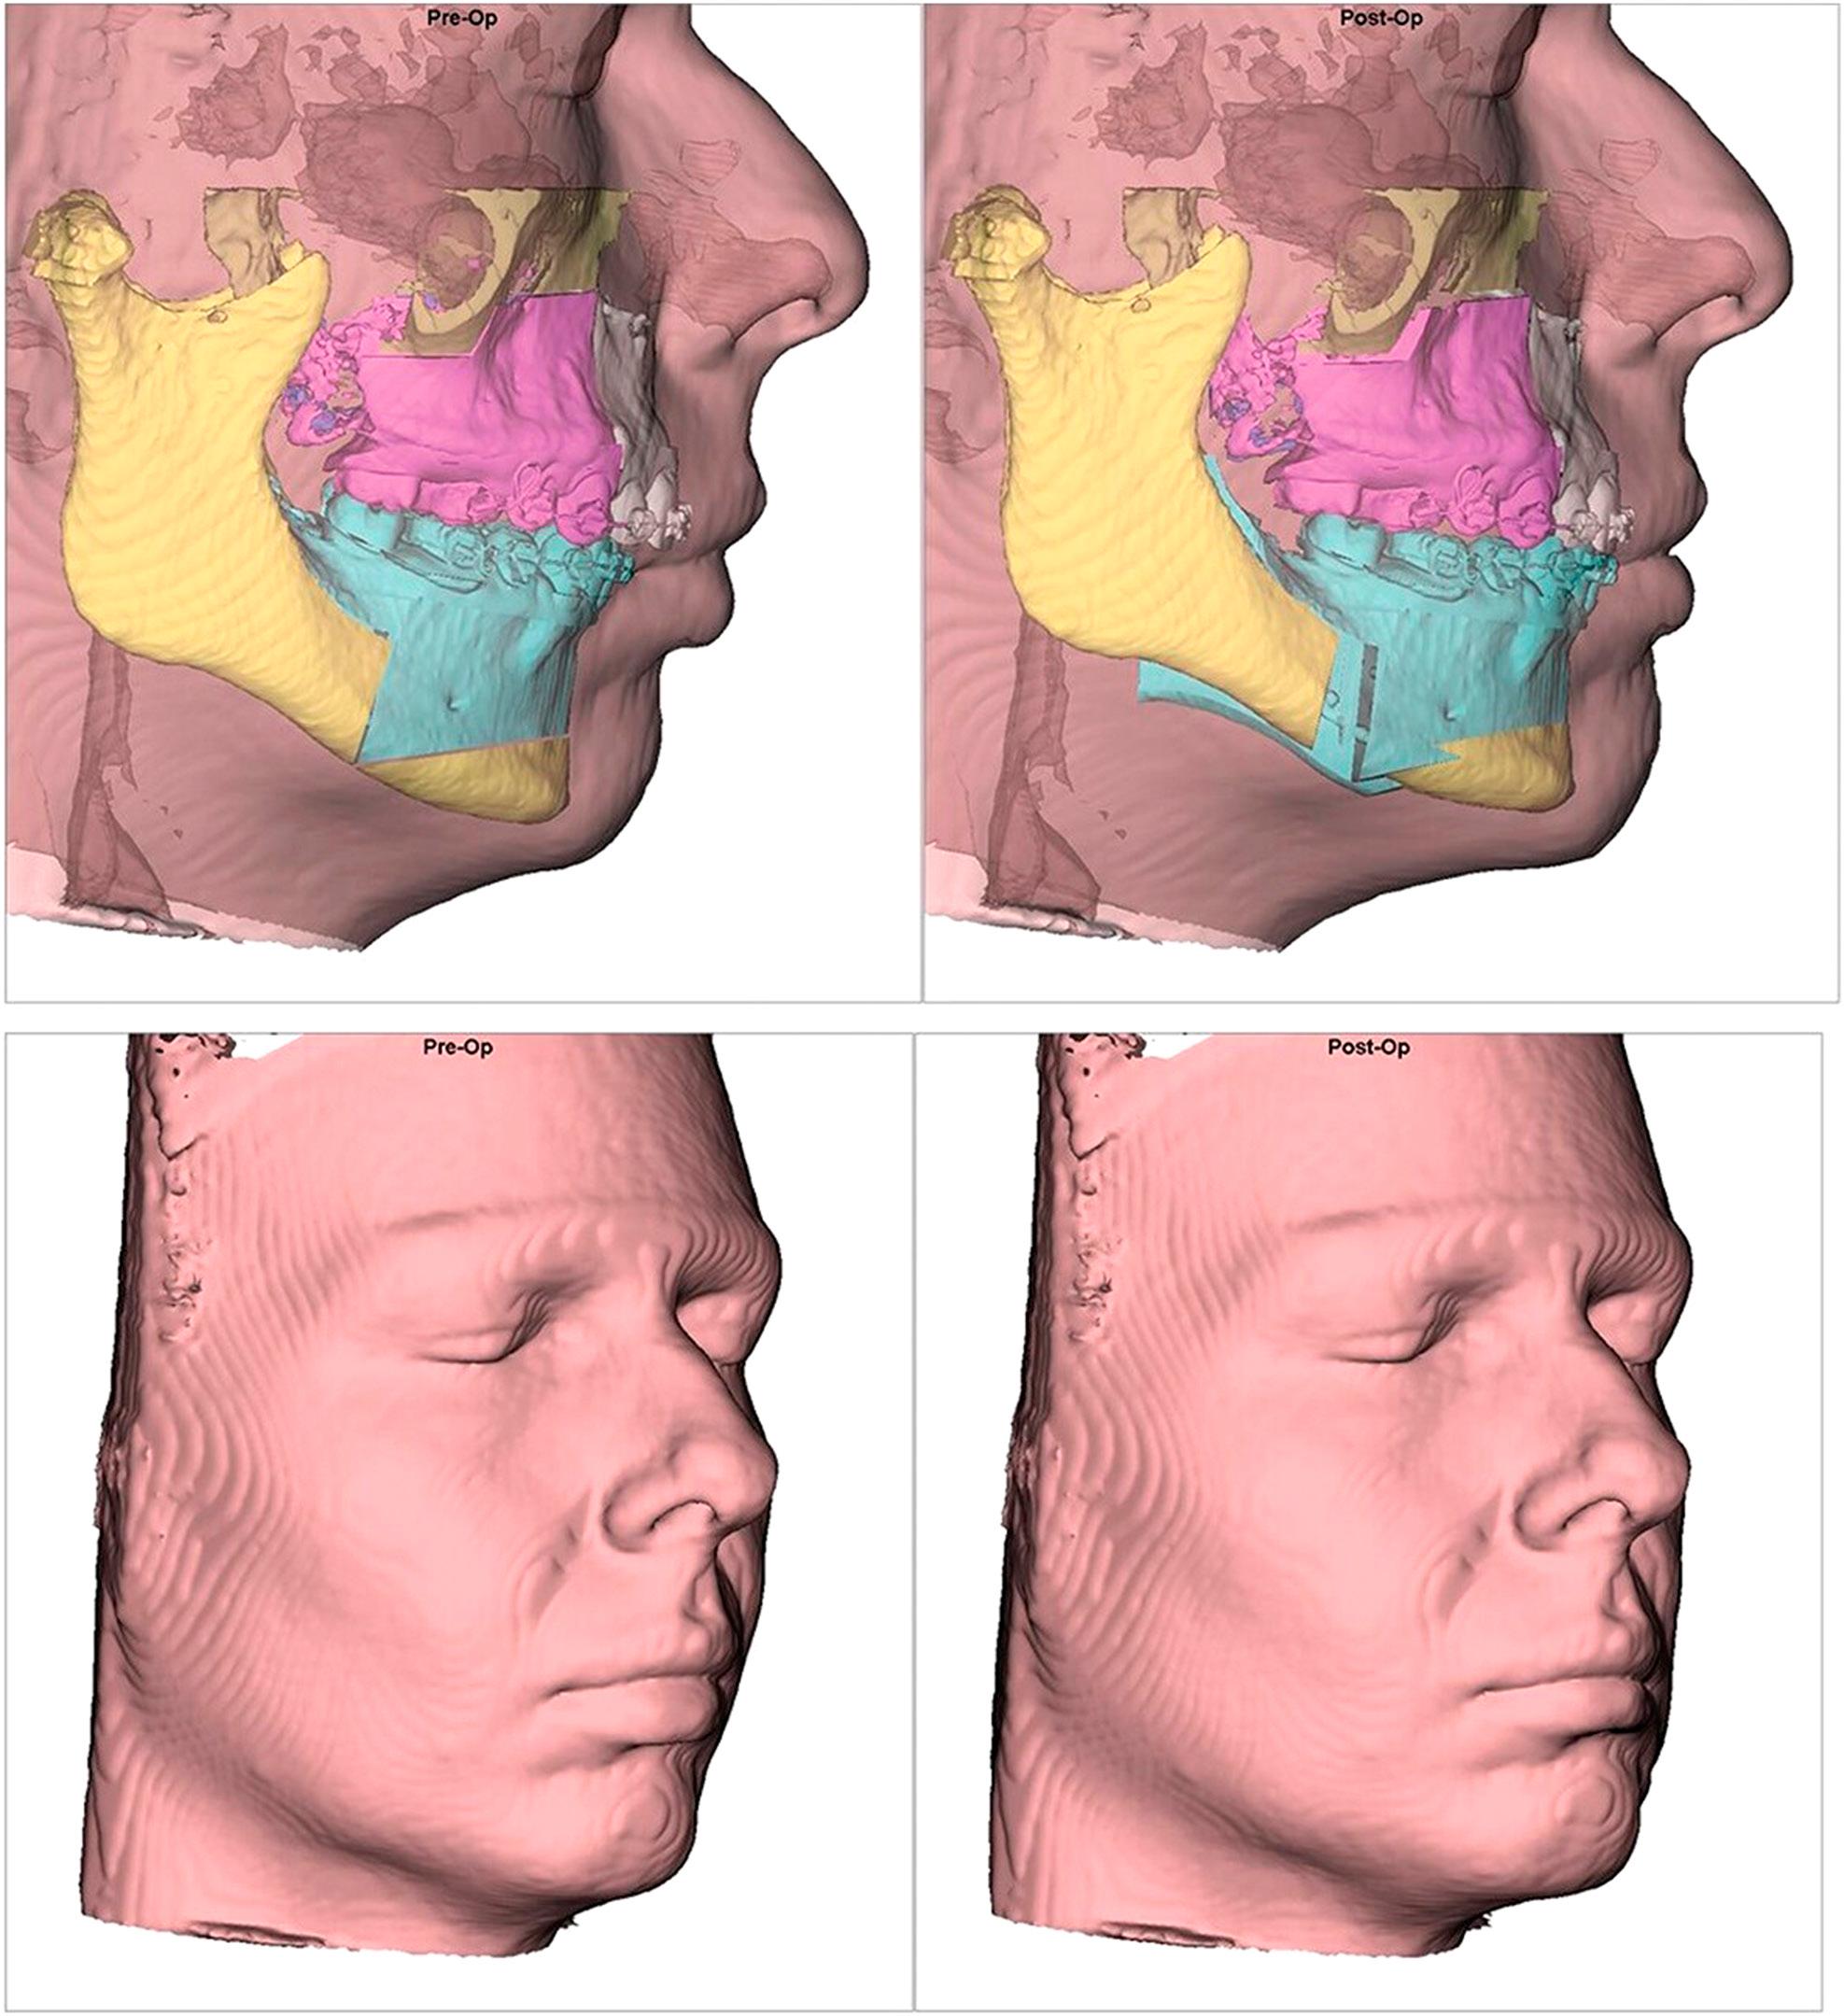

Figure 3.